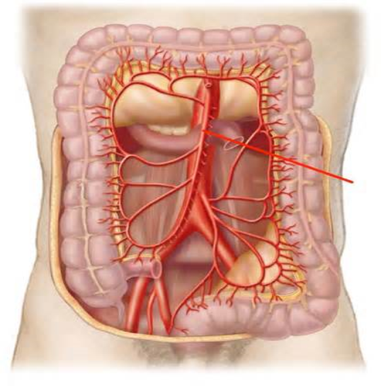

Cronh xəstəliyi mədə-bağırsağın hansı hissəsini tutur?

Klassik olaraq belə deyilir “ağızdan anusa qədər”

- yalnız nazik bağırsaqlar (ileit) – 20-30%

- nazik və yoğun bağırsaqlar (ileokolit) – 40-50%

- yalnız yoğun bağırsaqlar (kolit) – 20-30%

- perianal – 30%

- Digər seqmentlər (12bb, mədə və s) - 0,5-15%.

Crohn xəstəliyinin yayılma xüsusiyyəti necədir?

Nazik bağırsaq, kolon və ya hər ikisi zədələnə bilir, “sağlam aralar” yəni zədələnmiş bölgələr arasında sağlam bağırsaq toxuması olur, ona görə də regianal enterit də deyilir.